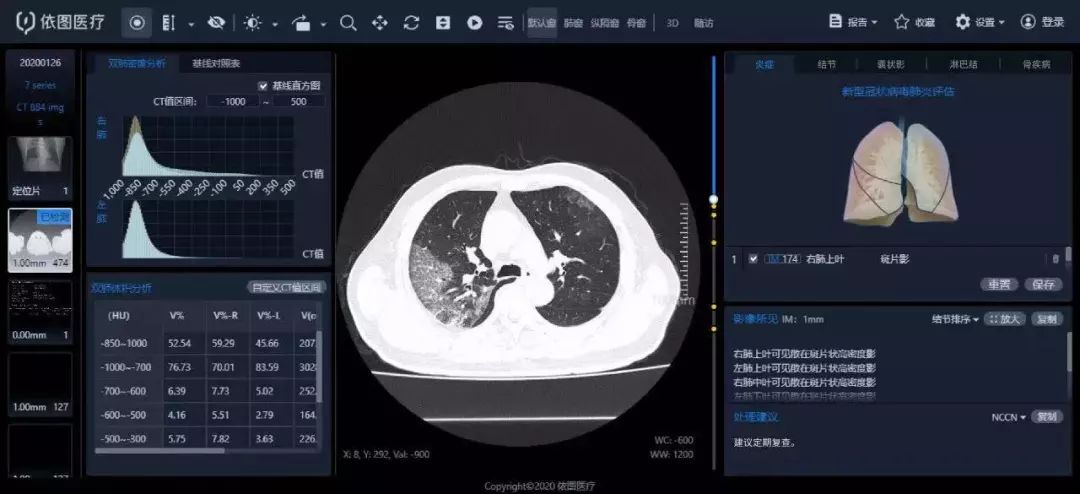

AI影像系统智能诊断,3秒完成定量分析

当前,新型冠状病毒性肺炎的疫情防控难点之一就是医疗资源高度短缺,尤其是医疗诊断这部分,短时间内的爆发式就诊需求难以实现快速精准诊断和分诊。

依图科技与上海市公共卫生临床中心(以下简称“公卫中心”)开发的新型冠状病毒性肺炎智能影像评价系统,近日在公卫中心上线。

“新型冠状病毒性肺炎智能评价系统”界面

这套系统实现了对新型冠状病毒性肺炎CT影像的智能化诊断与定量评价,可以对局部性病灶、弥漫性病变、全肺受累的各类肺炎疾病严重程度进行分级,精确测算出疾病累计的肺炎负荷,有助于临床判断病情。

相比传统手工勾画ROI的5~6个小时,它只需要2~3秒就能完成定量分析,提升精准定量分析的效率。

目前,这套系统也已经驰援武汉协和、武汉大学人民医院、武汉大学中南医院、温附一等医院。依图方面表示,疫情结束前,还将对定点收治医院免费升级部署。

此外,深睿医疗的两套Dr.Wise®肺部疾病智能解决方案(新冠肺炎增强版)系统及整套设备,也投入湖北省黄冈市中心医院新院区(大别山区域医疗中心)和荆州市第二人民医院季家台分院,帮助医生进行新型冠状病毒感染肺炎的影像诊断。

工作人员正在调试Dr.Wise®肺部疾病智能解决方案及整套设备

该系统是在原有的全肺AI辅助诊断系统的基础上,对新型肺炎的筛查功能进行了专门强化,可以针对各类原因导致的肺炎CT影像进行快速检测,也可帮助新冠肺炎的早期影像进行大规模病例筛查,及时发现潜在患者。